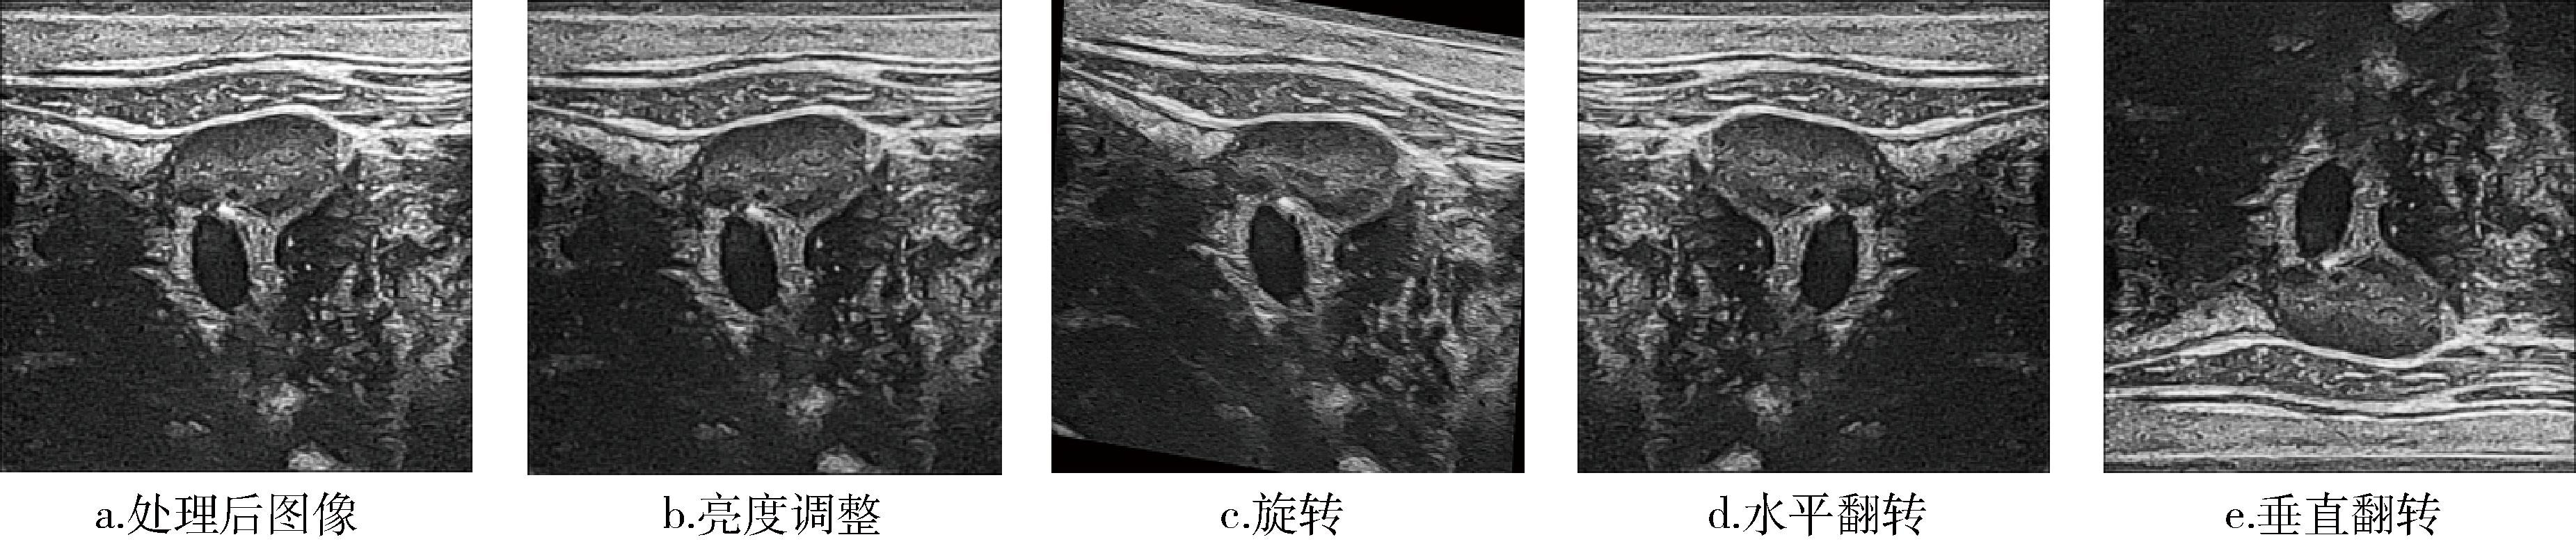

充分的数据量是提升模型性能的基础。医学数据具有一定的特殊性和保密性,数据量有限,因此在原有数据集的基础上进行数据增强。将图像亮度调整至(0.8,1.2)范围内,进行随机角度为(-30°,30°)的旋转操作,并以50%的概率进行水平翻转或垂直翻转,数据增强图片示例,见图8。这些增强方法有效提高了模型对多样化数据的适应性。

图8 数据增强图片示例